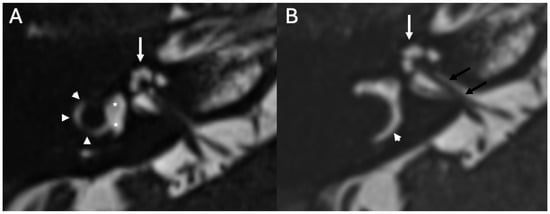

3.4. Labyrinthitis and Vestibulocochlear Neuritis

Imaging

| Labyrinthitis/Vestibulocochlear Neuritis | Taxak & Ram 2020 [32]; Kharrat et al., 2024 [33]; Singh et al., 2023 [34]; Kim et al., 2024 [35] | Case reports and small series | Meningitis can cause secondary labyrinthitis with cochlear enhancement on MRI; progression to ossification possible if chronic. |